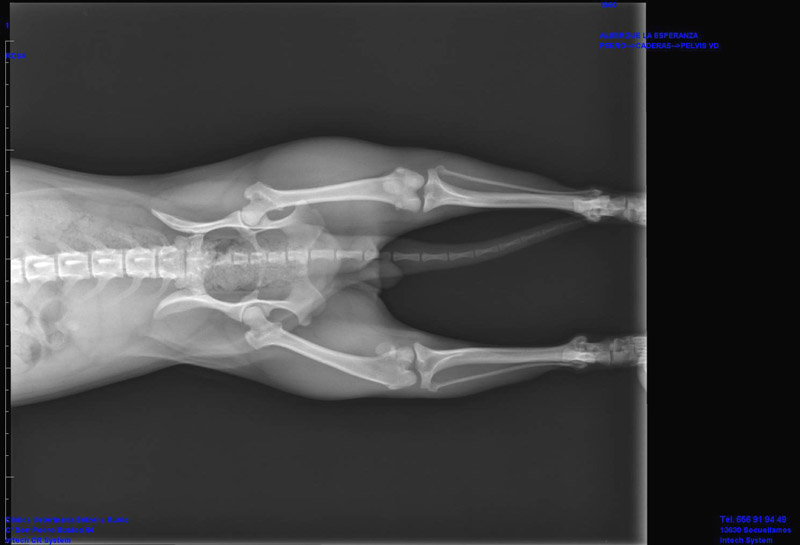

Glück hatte die kleine Rosa- rechtzeitig wurde das arme humpelnde Mädchen entdeckt.

In der Tierklinik wurde dann eine Patellaluxation diagnostiziert.

Vermutlich kann Rosa nächste Woche operiert werden.